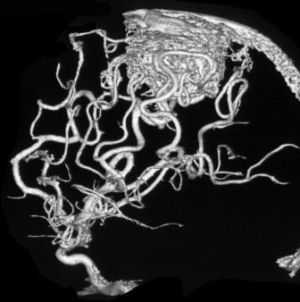

В целом, АВМ могут располагаться в любом полюсе головного мозга, причем как в поверхностных частях, так и глубинных слоях (таламусе и др.). Достоверно определить точную локализацию очага возможно только после прохождения аппаратного исследования с возможностями визуализации мягких тканей. К базовым принципам диагностики относят МРТ и метод ангиографии. Эти методы позволяют качественно оценить порядок ветвления артерий и построение вен, их соединение между собой, калибр ядра АВМ, афференты артерий, дренирующие вены.

Артериовенозные мальформации головного мозга — врожденные аномалии церебральных сосудов, характеризующиеся образованием локального сосудистого конгломерата, в котором отсутствуют капиллярные сосуды, а артерии напрямую переходят в вены. Артериовенозные мальформации головного мозга проявляются упорными головными болями, эпилептическим синдромом, интракраниальным кровотечением при разрыве сосудов мальформации. Диагностика осуществляется при помощи КТ и МРТ сосудов головного мозга. Лечение хирургическое: транскраниальное иссечение, радиохирургическое вмешательство, эндоваскулярная эмболизация или комбинация этих методик.

Поводом для обращения к неврологу до разрыва АВМ могут быть упорные головные боли, впервые возникший эпиприступ, появление очаговой симптоматики. Пациенту проводится плановое обследование, включающее ЭЭГ, Эхо-ЭГ и РЭГ. При разрыве АВМ диагностика осуществляется в экстренном порядке. Наиболее информативны в диагностике сосудистых мальформаций томографические методы. Компьютерная томография и магнитно-резонансная томография могут быть использованы как для визуализации тканей мозга, так и для исследования сосудов. В случае разрыва АВМ МРТ головного мозга более информативно, чем КТ. Она дает возможность выявить локализацию и размер кровоизлияния, отдифференцировать его от других объемных интракраниальных образований (хронической гематомы, опухоли, абсцесса головного мозга, церебральной кисты).

При торпидном течении АВМ МРТ и КТ головного мозга могут оставаться в норме. Обнаружить сосудистую мальформацию в таких случаях позволяет лишь церебральная ангиография и ее современные аналоги — КТ сосудов и МР-ангиография. Исследования церебральных сосудов проводятся с использованием контрастных веществ. Диагностика осуществляется нейрохирургом, который также оценивает операционный риск и целесообразность хирургического лечения АВМ. При этом следует учитывать, что при разрыве, в связи с компрессией сосудов в условиях гематомы и отека мозга, томографический размер АВМ может быть существенно меньше реального.